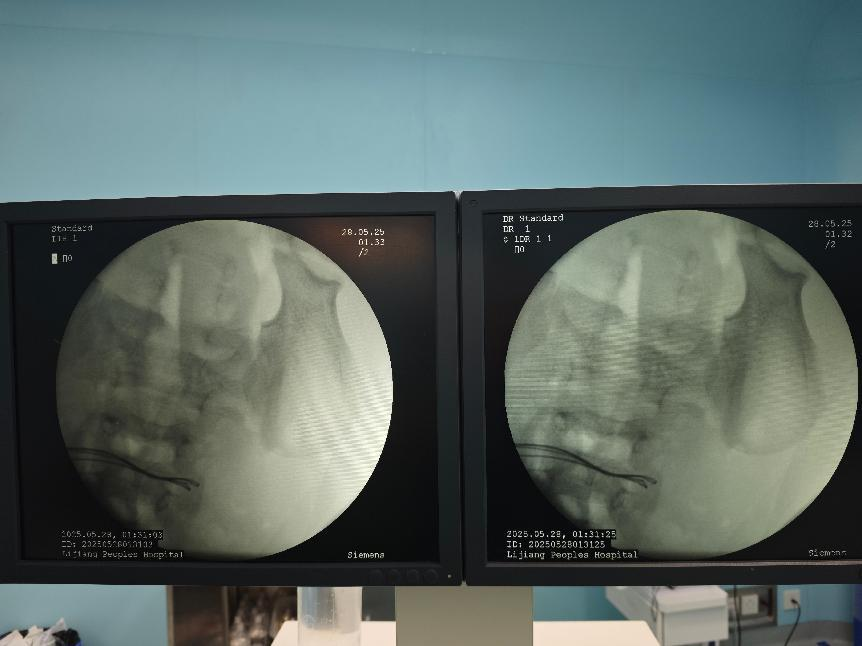

经过研判,医疗团队凭借着精湛的技术和坚定的信念,克服了重重困难,成功取出了该病人体内的37颗磁力珠,并对穿孔部位进行了细致的修补。经过数小时的紧张手术,通过腹腔镜、内的联合操作,让病人脱离了生命危险。

术中完善床旁DR见腹腔内已无异物